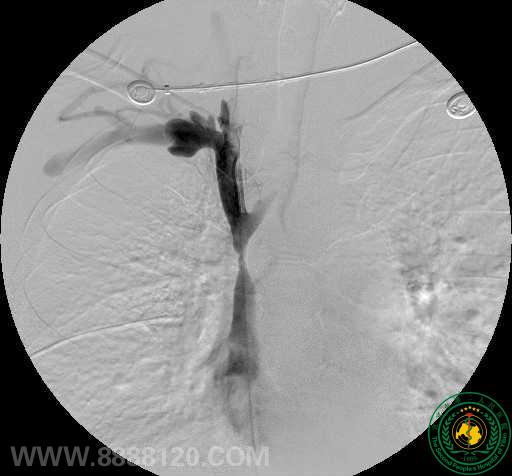

影像科介入组近日完成一例上腔静脉支架植入术

影像科介入组近日完成一例上腔静脉支架植入术3065